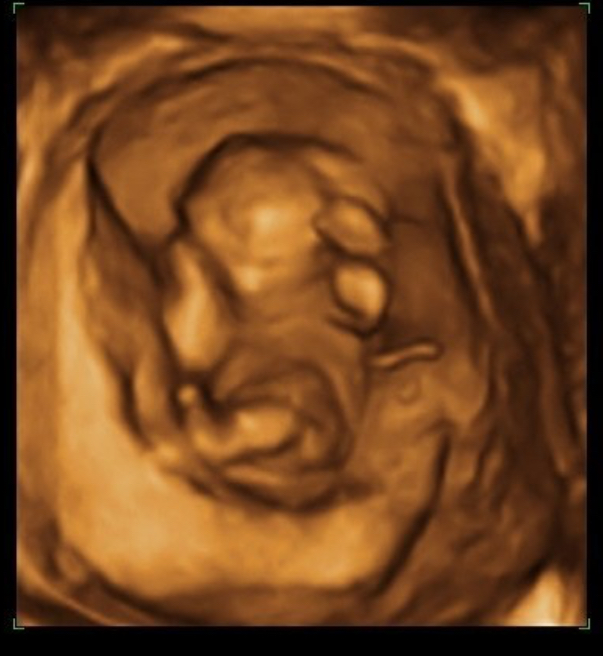

24 Haftalık Gebelik Ultrason Görüntüleri, Hareketleri

24 Haftalık Gebelik Hafta Hafta Hamilelik Anneysen

24. Hafta Gebelik